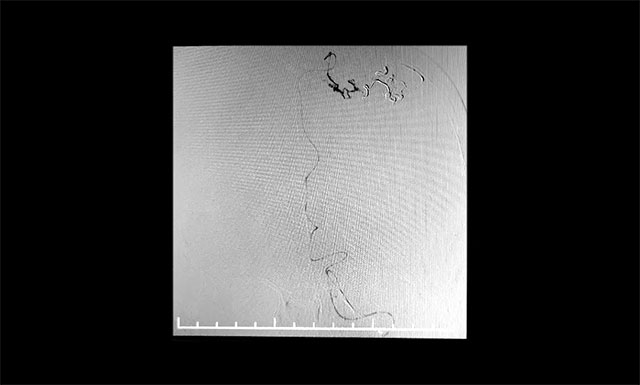

▲ 微導(dǎo)管造影確認(rèn)后,注入 Onyx 18膠

張琪博士團(tuán)隊(duì)制定了嚴(yán)密的手術(shù)計(jì)劃,預(yù)料各種術(shù)中、術(shù)后可能出現(xiàn)的意外及并發(fā)癥。7月12日行動(dòng)靜脈畸形介入栓塞術(shù),術(shù)中導(dǎo)管在動(dòng)靜脈畸形部位緩慢推注Onyx18生物膠,DSA透視下顯示膠在畸形中彌散良好,無明顯反流,順利栓塞。